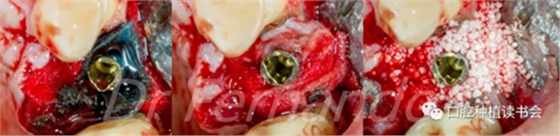

首先去除了螺絲固位的牙冠,引流膿液,翻全厚瓣暴露受感染部位的種植體。對暴露種植體進行種植體成形術(shù),金剛砂車針磨除種植體表面凹槽(圖 20)。

圖20 種植體周圍有膿液滲出,翻瓣后行種植體成形術(shù)

然后根據(jù)種植體周圍炎的標準治療程序,先使用磷酸&氯己定凝膠處理種植體表面2分鐘后,接著使用抗生素溶液(透明質(zhì)酸鈉哌拉西林他唑巴坦)處理5分鐘,然后使用Cerasorb ?M 骨粉植骨(Curasan?-科盧森)(圖 21)。

圖21 機械&化學凈化種植體表面后,使用Cerasorb ?M 骨粉植骨